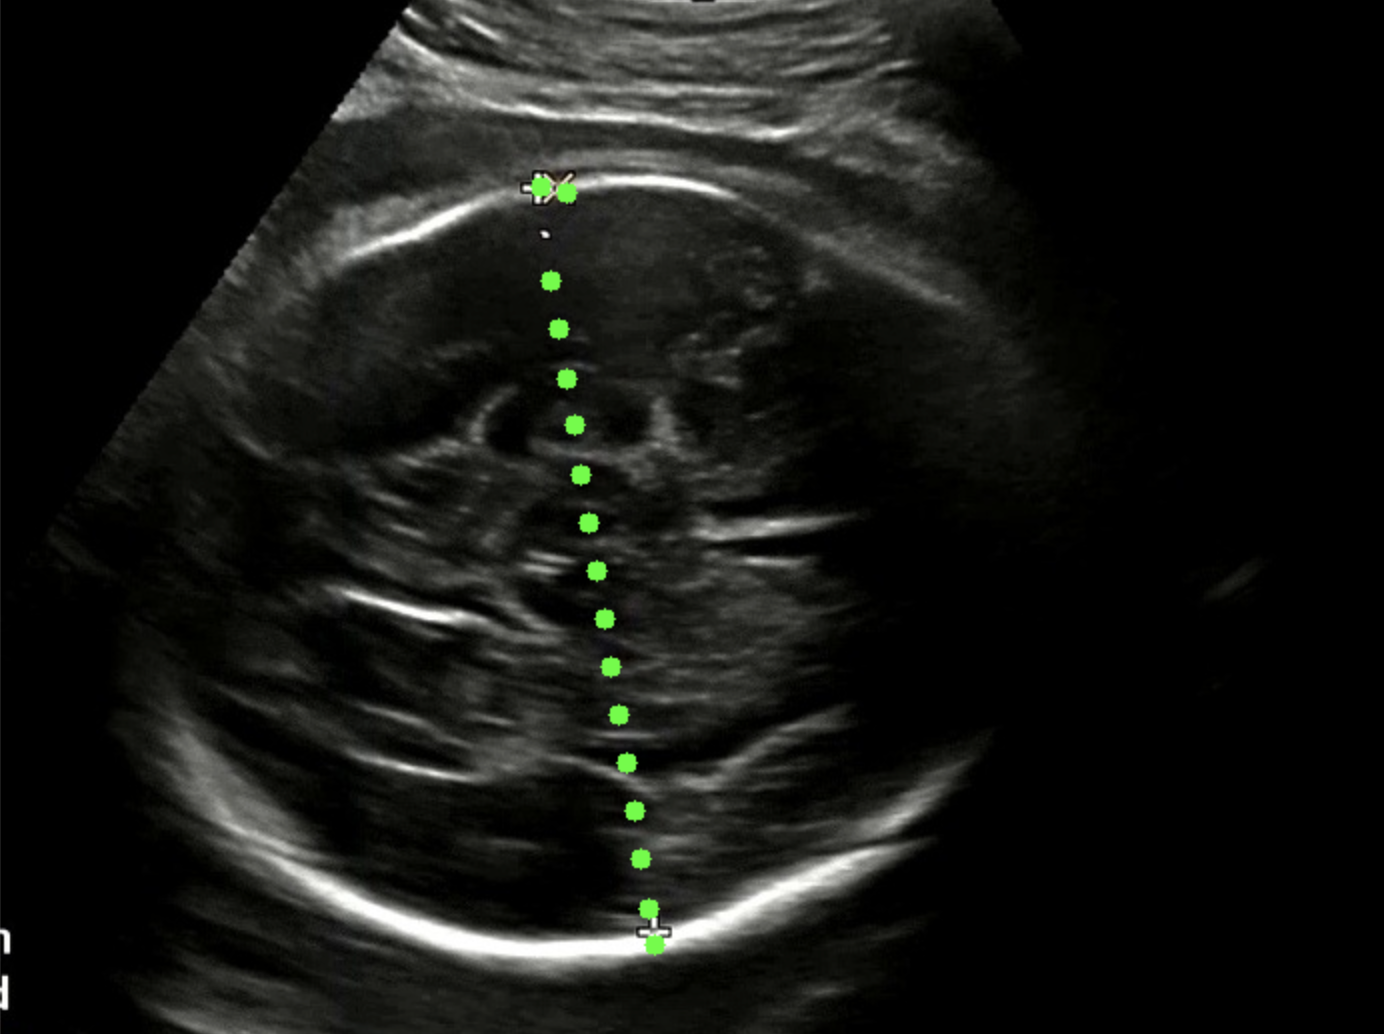

점선 패턴을 인식하는 방법을 선택했다. 점선 패턴은 BPD 를 측정할 때 모든 영상에 출력된다. 그리고 우리는 개발자이기 때문에 의사의 판단을 넘어서는 행위를 하면 안 된다고 생각했다. 그래서 점선 패턴을 인식하고 같은 선상에 있는 점들을 찾아냈다. 그리고 찾아낸 점들 중 가장 먼 좌표 간 거리를 계산하여 픽셀 거리를 획득했다.